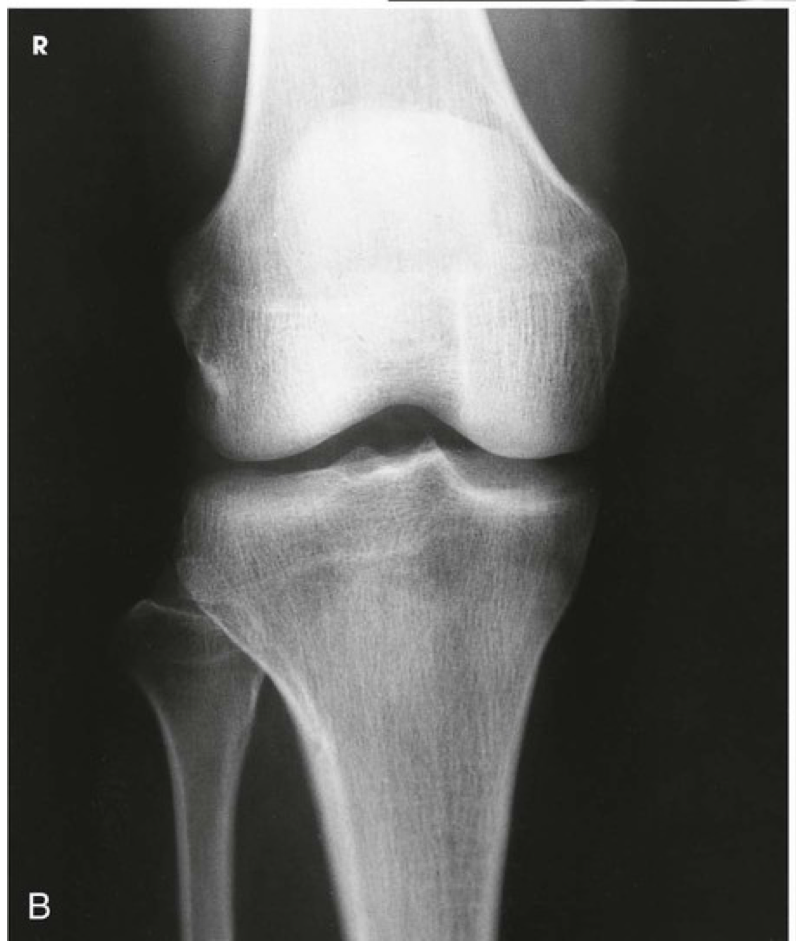

Question 7

Question

Label the image

Image:

a9cde9c5-788d-4b9d-9f46-6a3e0c0ec46a (image/png)

Answer

patella

medial femoral condyle

lateral femoral condyle

medial tibial plateau

lateral tibial plateau

medial tibial codyle

lateral tibial condyle

tibiofibular articulation

fibula

tibia